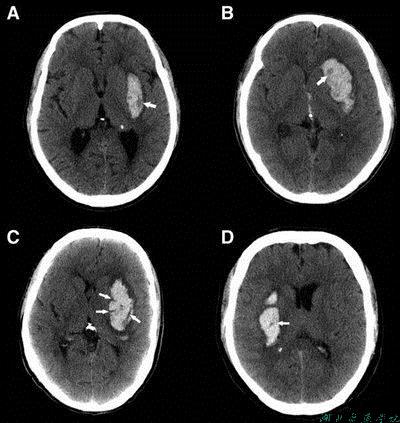

2.CT诊断:方便快捷,清晰显示脑组织,区分脑出血和脑梗死;确定部位、大小、性质等,急性卒中首选方法。

图13 脑出血CT影像